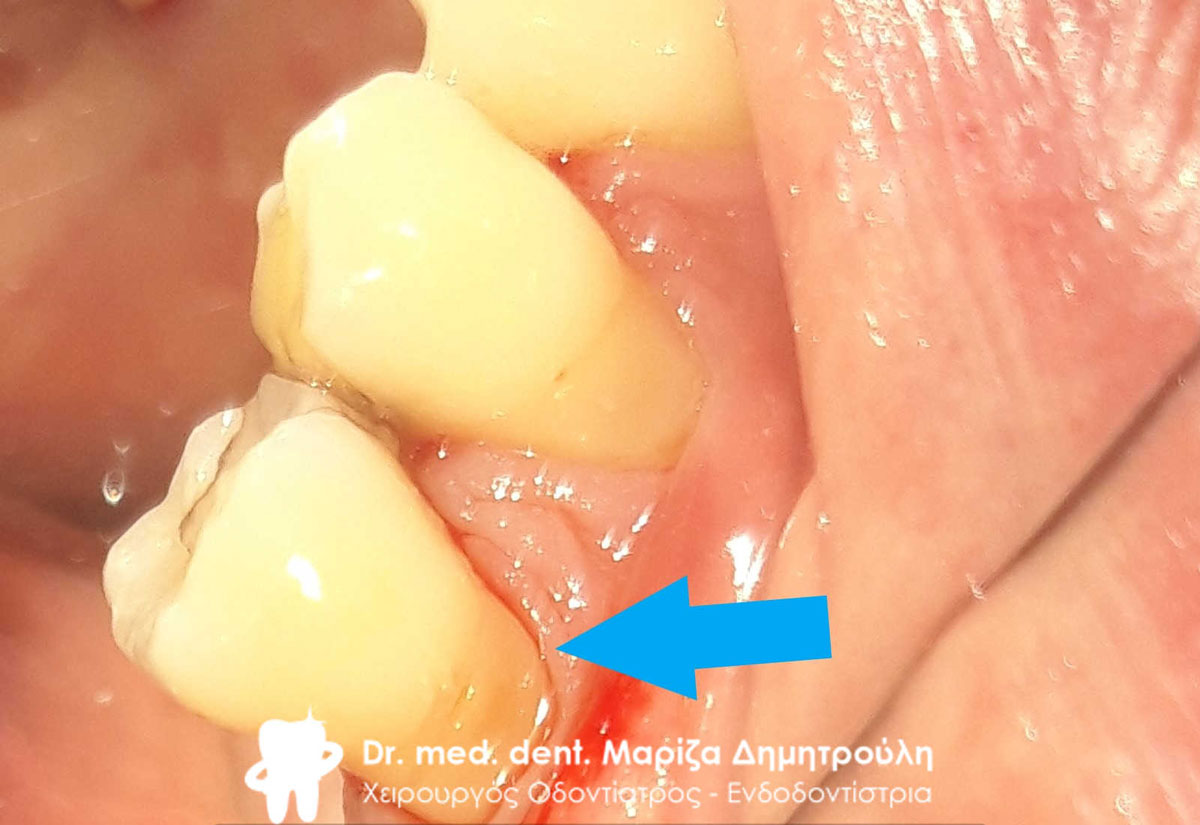

Ο ασθενής επιθυμούσε την αισθητική αποκατάσταση μιας “μαυρίλας”, όπως πολύ χαρακτηριστικά ανέφερε κατά την επίσκεψη του στο ιατρείο. Αρχικά η αλλοίωση τροχίστηκε, αφαιρέθηκε η τερηδόνα (όπως δείχνει η 2η φωτογραφία) και στη συνέχεια το έλλειμα αποκαταστάθηκε με λευκό σφράγισμα ρητίνης.

ΠΡΙΝ

Το δόντι καθαρό μετά την απομάκρυνση της τερηδόνας